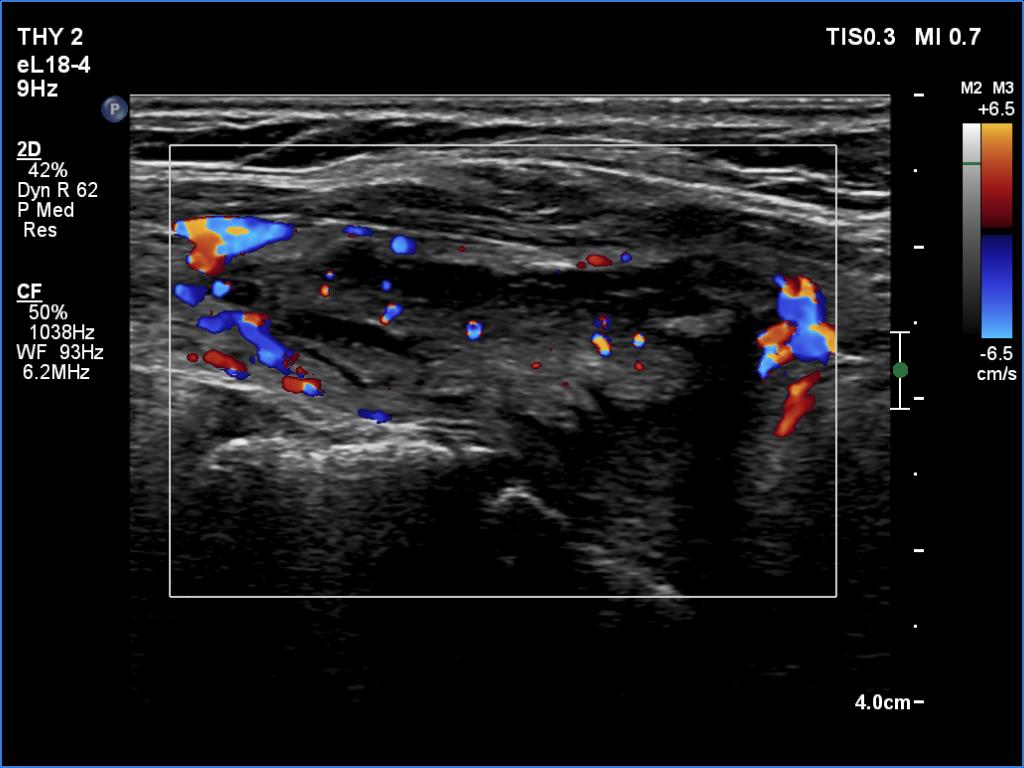

In the first part of the ultrasound examination, when the transducer was continuously moving over the thyroid gland, it was not detectable that the contents of the nodule were showing flow. When we stopped the transducer, it became clear that the seemingly solid mass was actually a dense liquid in a continuous flow. On Doppler examination, 'circulation' was visible in continuously changing places.

If it had really been about blood vessels, according to the cycle of circulation,

it would have disappeared once, at other times the flow would have reappeared, but at the same time we would have always seen it in the same place.

This case illustrates two rare phenomena. On the one hand, a dense liquid may appear to be a solid tissue. On the other hand, the Doppler assay actually detects fluid flow. In the vast majority of cases, of course, this displays a circulation in the blood vessels, but in the case of cysts, when pressure is applied to the fluid with the probe, a flow is created. In the case of flow in blood vessels, circulation is always seen in the same place, while in the case of flowing cystic fluid, the flow can be detected in constantly changing places.